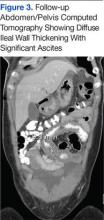

While in the ED, the patient’s physical exam revealed mild tachycardia (104 bpm on arrival, which improved with fluid resuscitation) and diffuse abdominal tenderness. Laboratory evaluation revealed a mild leukocytosis (10.7 x 103/L) but normal liver-associated enzymes, lipase, and urinalysis. A computed tomography (CT) scan of the abdomen and pelvis with oral and IV contrast revealed diffuse ileal wall thickening with significant perihepatic and perisplenic ascites with pelvic free fluid suspicious for an inflammatory vs infectious enteritis (Figure 1).